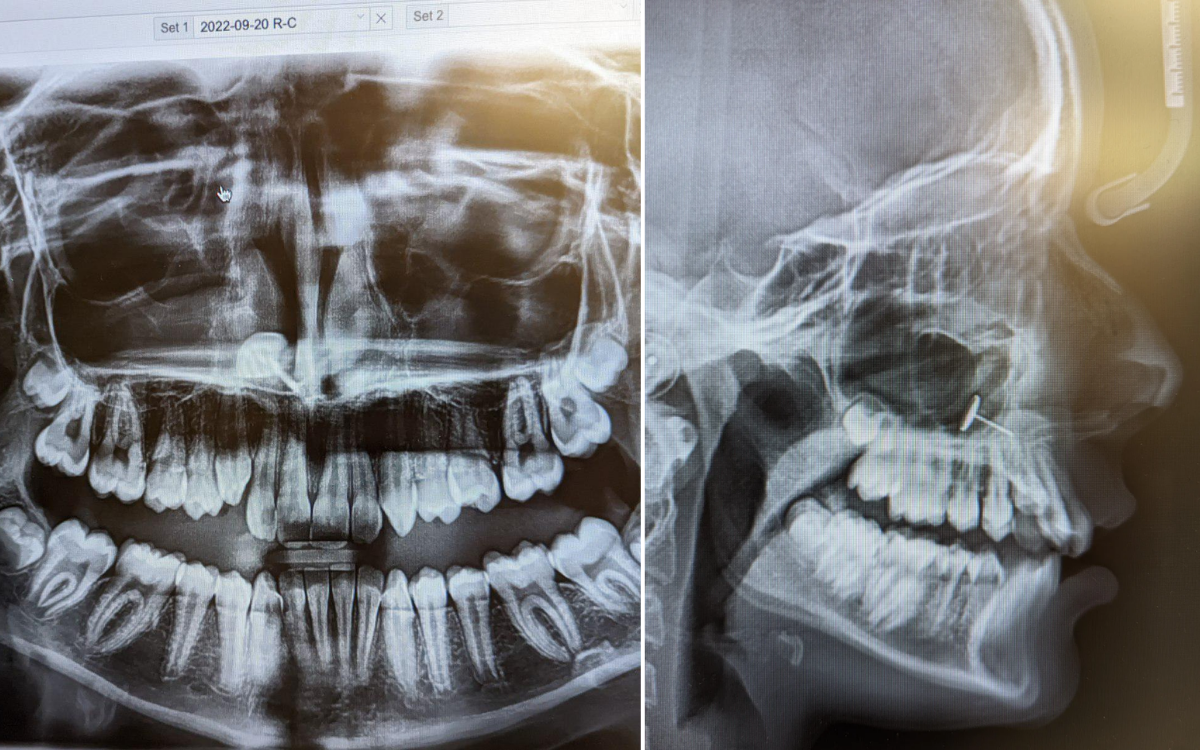

# Teen Secretly Pierces Her Own Nose, X-ray Reveals Hidden metal

“The orthodontist came back into the room and put the X-rays on the screen,” Ophelia told *Newsweek*. “we all saw it at the same time and spent several minutes trying to figure out what we were looking at.”

What they were looking at appeared to be a small piece of metal that was lodged in her daughter’s sinuses. Ophelia was at a loss to explain how it had gotten there, but one person in the room knew exactly what had happened: her daughter.to understand how they got to this point, you have to go back six months to when Ophelia’s daughter, who had only just turned 13, asked her mom if she could get her nose pierced.

“Apparently, at some point, she decided to try to push it through from the inside,” Ophelia said. “I’m not sure if she sneezed or what happened, but she ended up inhaling the earring. It got stuck in her sinuses.”